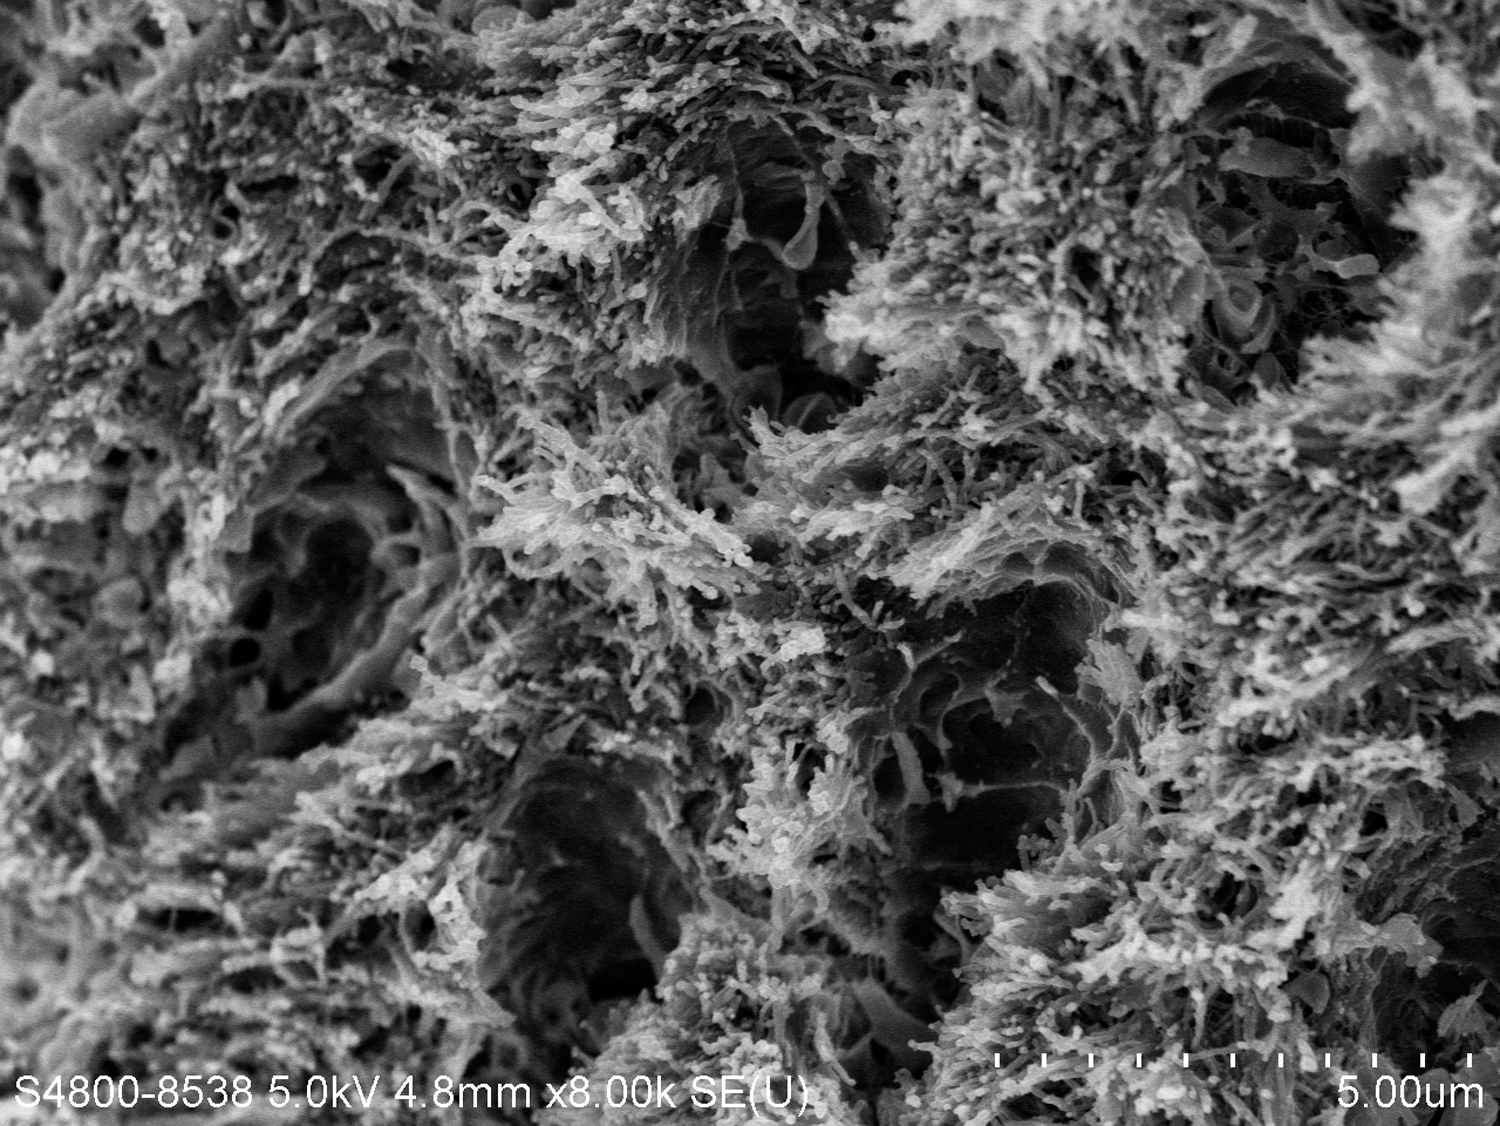

There are several advantages of using SDF in dental treatment. First, it showed an antimicrobial activity against mono-species, dual-species, and multi-species cariogenic biofilm.14-16 Silver ions are bactericidal metal cations that inhibit biofilm formation.17 Studies have indicated that silver interacts with sulfhydryl groups of proteins and DNA, thus altering hydrogen bonding and inhibiting respiratory processes, DNA unwinding, cell-wall synthesis, and cell division.18 At the macro level, these interactions affect bacterial killing and inhibit biofilm formation.17 Second, fluoride promotes caries lesion remineralization. Fluoride has been indicated to react with hydroxyapatite and generate calcium fluoride, which is a reservoir of fluoride, and facilitate further remineralization.19 An ex vivo study reported surface microhardness of the surface layer of the arrested caries after SDF applications was comparable with the unaffected sound dentin20 (Figure 1 and Figure 2). This is consistent with another study, in which a high remineralized zone was observed on the surface of arrested caries from exfoliated teeth with SDF treatment21 (Figure 3 and Figure 4). Third, its application procedures are simple and do not require injection or drilling, and the treatment does not involve expensive support infrastructure equipment such as piped water and electricity. The simplicity of the treatment is conducive to treating caries in apprehensive young children who may have intense dental fear, uncooperative patients with special needs, or elderly patients who have difficulty adapting to traditional dental care. It also allows trained workers to deliver the treatment to people who live in the area but who may not be able to easily access dental service.22 Patient compliance and satisfaction is often good when the patient is provided a clear explanation of the treatment outcome.23,24 Finally, the cost of SDF treatment is low and should be affordable in most communities.

Fig 3. Scanning electron microscope (SEM) images of the dentin carious lesions. Fig 3: Surface morphology of arrested carious lesion. Fig 4: Surface morphology of active carious lesion. (images from Mei, et al, 201421 [reprinted with approval])

Figure 3

Fig 4. Scanning electron microscope (SEM) images of the dentin carious lesions. Fig 3: Surface morphology of arrested carious lesion. Fig 4: Surface morphology of active carious lesion. (images from Mei, et al, 201421 [reprinted with approval])

Figure 4